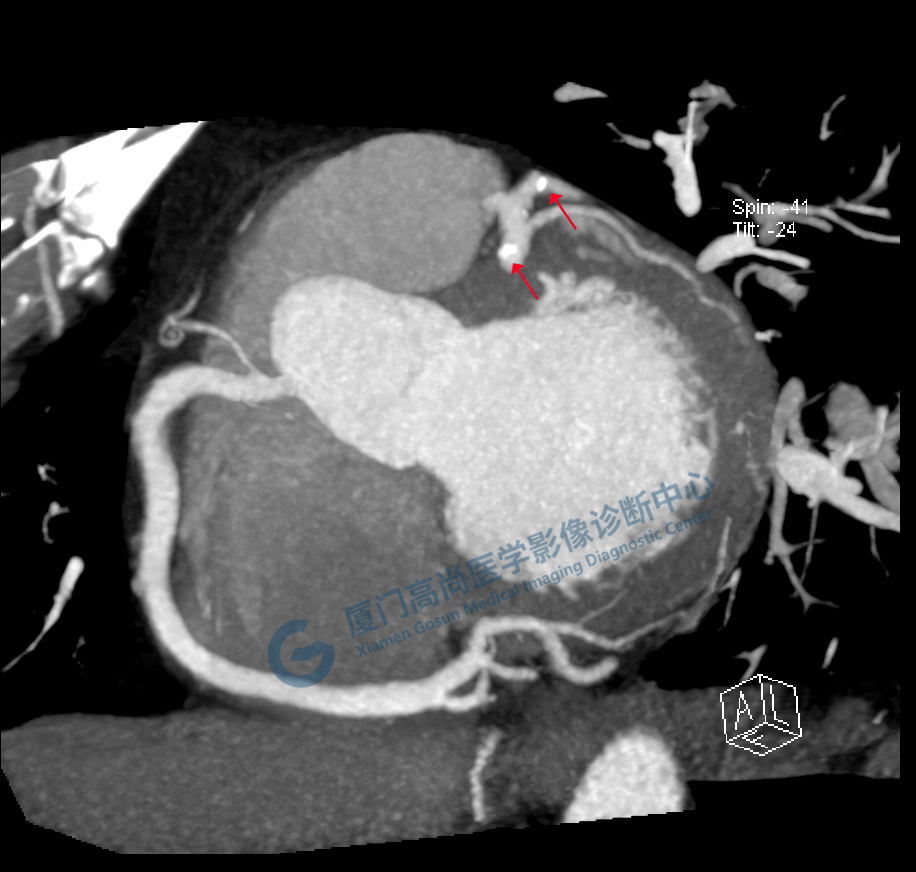

冠脈CTA圖像

左、右冠開(kāi)口

冠狀CTA右冠

回旋支

前降支

圖像所見(jiàn):左冠狀動(dòng)脈前降支,前降支近段可見(jiàn)局部鈣化斑塊,管腔狹窄約5%,左側(cè)冠狀動(dòng)脈對(duì)角支可見(jiàn)鈣化斑塊,管腔狹窄約20%-30%。

左冠狀動(dòng)脈回旋支,近段可見(jiàn)局部鈣化斑塊,管腔狹窄約5%-10%。

影像診斷:CAD-RADS分級(jí):2(25%-49%),輕度狹窄。